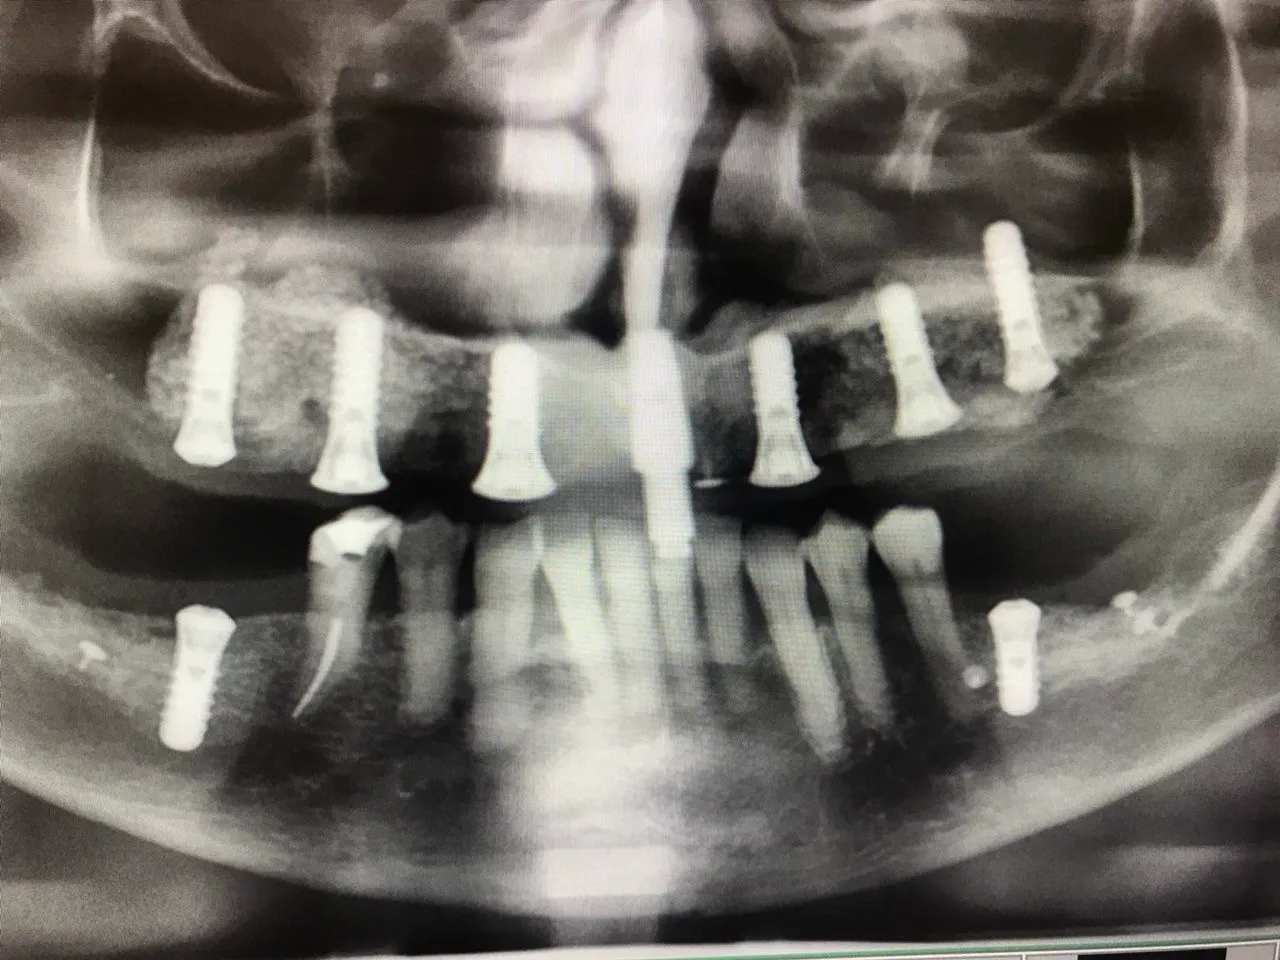

Dual Arch Rehabilitation — All-on-4 & All-on-6

Complete upper and lower jaw rehabilitation. All-on-4 concept for maxilla and All-on-6 for mandible with custom surgical guides.